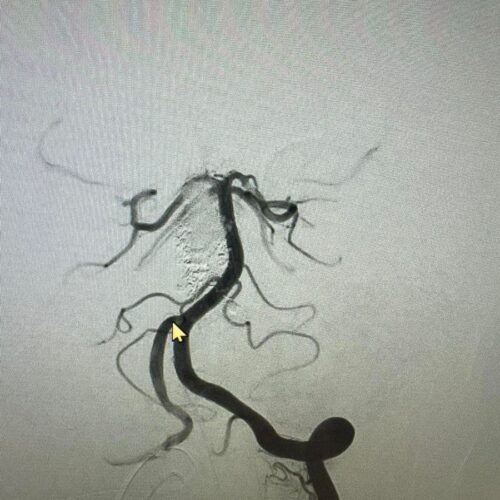

Δια ζώσης συμμετοχή των φοιτητών του Πανεπιστημίου Πατρών σε εξειδικευμένες τεχνικές ενδοαγγειακής αντιμετώπισης αγγειακών δυσπλασιών του κεντρικού νευρικού συστήματος.

Στην επέμβαση συμμετείχαν ο Καθηγητής Ενδοαγγειακής Νευροχειρουργικής Κος Β. Παναγιωτόπουλος, ο Καθηγητής Επεμβατικής Νευροακτινολογίας κος Π. Ζαμπάκης, ο επιμελητής επεμβατικής ακτινολογίας κος Μ. Θεοφάνης και ο αναισθησιολόγος κ. Γούδας.